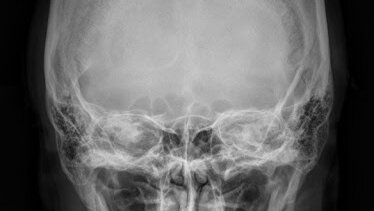

РЕНТГЕН ЧЕРЕПА ЧТО ЭТО Рентген черепа — это 2-х мерное рентгеновское исследование, проводится в двух проекциях (прямой и боковой). Снимок охватывает все кости черепа, включая верхнюю и нижнюю челюсть, а так же турецкое седло. ДЛЯ ЧЕГО Рентген черепа может быть назначен в следующих случаях: КАК ПРОВОДИТСЯ Пациента укладывают на специальный рентгеновский стол, снимок проводится в двух проекциях, прямая проекция — лежа на животе лицом вниз, боковая — то же на животе, только голова поворачивается на необходимый врачу бок...

Поводы для назначения рентгенограммы можно разделить на две категории: жалобы пациента и клинические проявления, наблюдаемые самим врачом. Если вы жалуетесь на дрожание рук, головные боли, потемнение в глазах, кровотечение из носа и головокружение, болезненное жевание, потерю слуха и нарушение зрения, будьте готовы к тому, что врач направит вас на рентген. Рентген черепа также показан при: черепно-мозговой травме (наиболее частое состояние), развитии асимметрии лицевых костей, обмороках, подозрении на опухоли, врожденных поражениях черепа и эндокринных аномалиях...